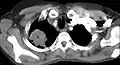

مسح بالأشعة المقطعية يُظهِر ورم بانكوست ( موضَّح بحرف P، سرطان الرئة ذو الخلايا غير الصغيرة، الرئة اليمنى) لرئة امرأة مدخنة تبلغ من العمر 47 عاماً.